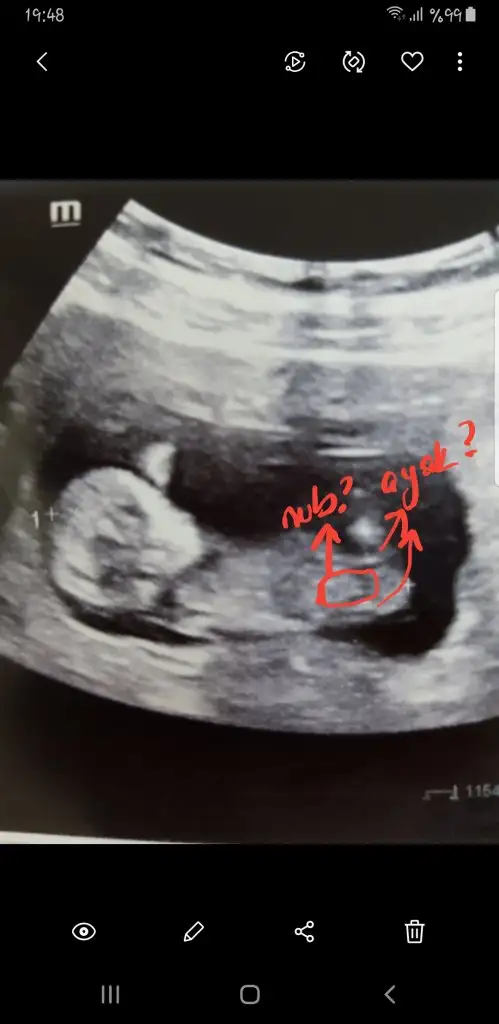

Kız gibi geldi nubu banaMerhabalar, benim de usg tam 12+0 haftalık, dr net konuşmamakla birlikte erkek gibi ama kesin bir şey demeyeyim dediyorumlarsanız çok sevinirim

Aslında okla gösterdiğiniz yeri ben ayak olarak düşündüm deKız gibi geldi nubu banaumarım gonlunuzdeki olsun inşallahEki Görüntüle 2748350

USG net değil gördüğüm nub ise erkek sanki kaç haftalık USG

12 haftalıkUSG net değil gördüğüm nub ise erkek sanki kaç haftalık USG